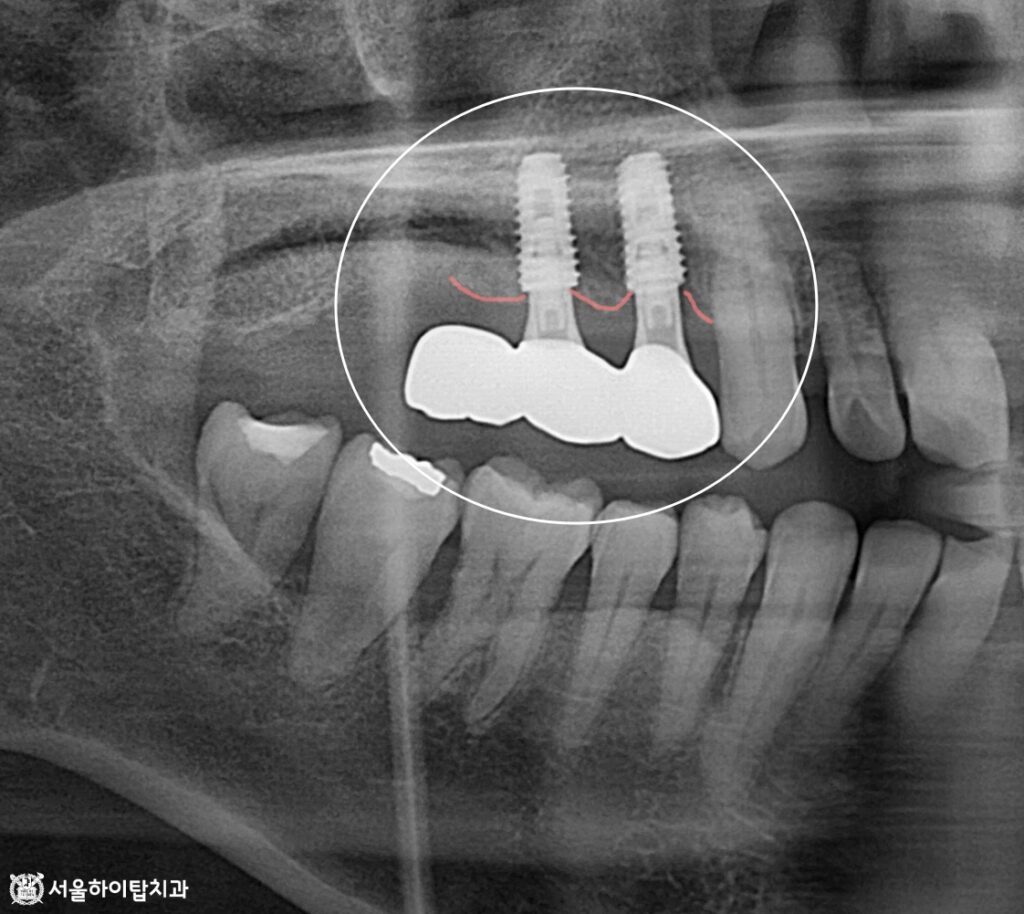

골 유착 후 스캔바디 체결

이제 뼈와 임플란트가 단단히 결합되는

골유착(Osseointegration) 과정을 약 4개월 정도 거친 뒤,

스캔바디(Scan body)를 체결하여 디지털 스캔을 진행합니다.

스캔바디를 이용하면 정확한 위치와 각도, 깊이 정보를 얻어

최종 보철 제작에 활용할 수 있습니다.

최종 결과 – 지르코니아 크라운 장착

최종적으로 지르코니아 크라운이 장착되면서,

심미성과 저작 기능이 동시에 개선된 모습을 확인할 수 있습니다.

어금니 부위는 폰틱(Pontic)으로 처리되었지만,

교합과 연조직 형태가 잘 맞춰져 있어 저작 기능과 심미 모두 안정적으로 유지됩니다.